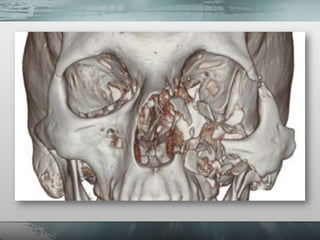

• São fraturas resultantes de impactos com

grande energia.

• Apresentam aspecto

clínico agressivo.

• Alto custo financeiro

de retorno do

paciente ao convívio

social.

• Alto índice de

sequelas

• São tratamentos

complexos.

• Muitas vezes

exigem diversas

cirurgias.

• Grande morbidade.